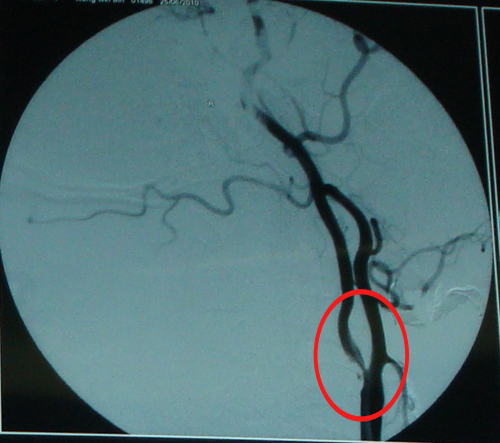

DSA示:右侧颈内动脉近端重度狭窄

该患者颈内动脉狭窄严重,伴有言语不清(TIA发作),有高脂血症,属高危人群,故符合CEA手术指征。2010年7月4日,由协作组张勤奕教授前往大同同煤集团总医院为其实施了右侧颈内动脉CEA。